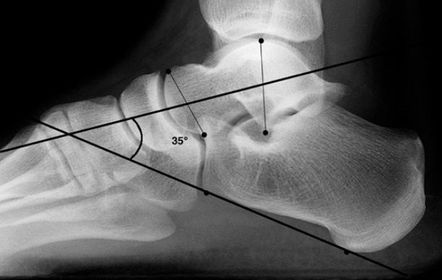

What is this angle called? What is normal? What does an increased angle indicate? | Talo-calcaneal angle. 25-45 degrees. Increased angle = hindfoot valgus |